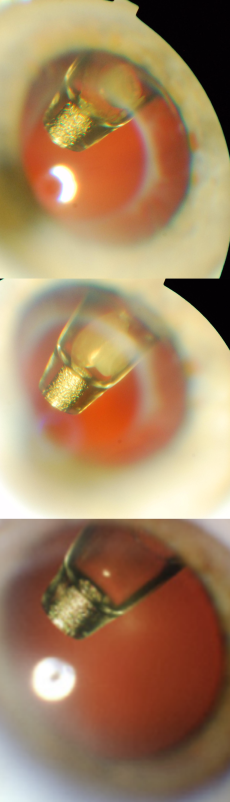

Video depicting insertion of the refill-exchange needle through the septum of the PDS implant, followed by refill-exchange (simultaneous extraction of implant contents into the needle tip and replacement with fresh drug).

Refill-Exchange Procedure

The PDS implant is refilled during a minimally invasive in-clinic refill-exchange procedure using the specially designed PDS refill needle, via the self-sealing septum.[16] The refill needle is a 34G double cannula with a vented needle and fluid collection reservoir that enables exchange of the implant contents with fresh ranibizumab 100 mg/mL. One 100-µL refill-exchange stroke can remove over 98% of the implant contents and replace it with fresh drug. Previous contents are exchanged fresh medication in a single stroke, with no significant bolus during the procedure.

The innovative refill-exchange procedure should be approached differently than an intravitreal injection as it requires precise targeting and a strictly perpendicular approach. The refill-exchange procedure should be performed under strict aseptic conditions with optimization of visualization, using magnification and task lighting to set the stage for refill-exchange success.

Of note, if there is any significant resistance encountered, withdraw the refill needle. Increased pressure will not overcome imprecise alignment. Do not tilt or twist if there is resistance, as it may bend the needle or cause damage to septum or overlying tissue. Reorient and insert again, taking care to ascertain perpendicularity, alignment, and good visualization.

The refill needle achieves a “soft stop” which must remain in contact with the conjunctiva throughout the refill-exchange procedure, which should be done slowly over ~5–10 seconds. Use of a cotton-tipped applicator also helps to stabilize the globe and minimize eye movement. Precise targeting to the septum center with a perpendicular approach is key for success.

The PDS refill-exchange procedure differs from intravitreal injection and requires a unique and precise skillset. The experiences during refill-exchange in clinical trials have informed the evolution and refinement of PDS procedures. Adherence to the refill-exchange procedure methodology maximizes optimal outcomes.